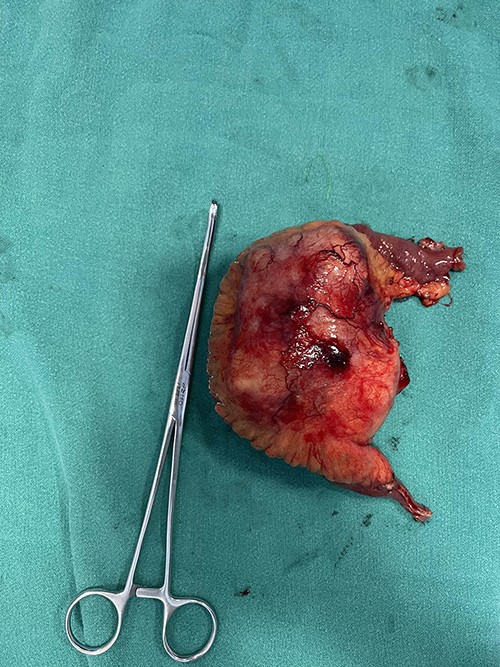

Patient was admitted. Midline laparotomy was done. Peritoneal cavity was explored. Large lipomatous mass measuring 13 cm × 8 cm was found at ileal mesentery at ~70 cm from ileocecal junction. Mass was well defined with invasion into the bowel and the ileal arteries. Mass was excised in toto along with involved ileum attaining macroscopically negative margins. Bowel continuity was maintained with end-to-end anastomosis (Fig. 3). Postoperative period was uneventful.

Gross examination revealed large lobulated mass of size 12 cm × 10 cm × 7 cm, weighing 817 g. The cut section showed yellow soft to firm areas with some hemorrhagic areas. Eosin and hematoxylin stain revealed area of lipoblast, pleomorphic cell, mitotic figures with multiple areas of necrosis (Figs 4, 5 and 6). Immunohistochemical reaction showed positivity for S-100 protein, mouse double minute 2 (MDM-2), cyclin-dependent kinase 4 (CDK4) and p16 which helped us differentiate it as dedifferentiated liposarcoma.